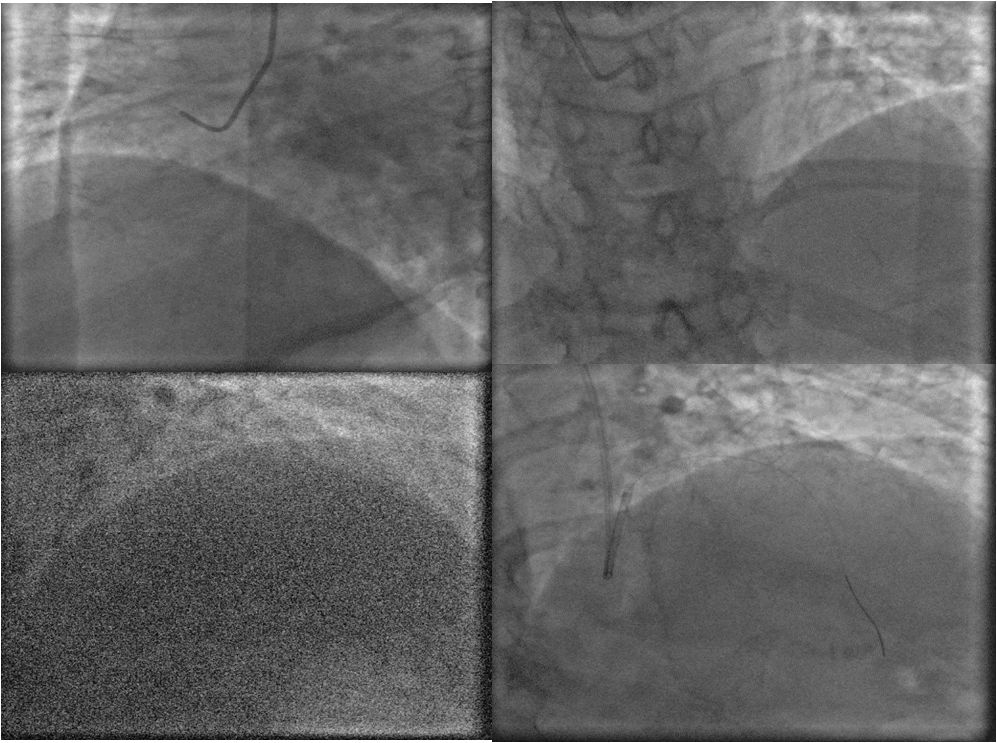

LM狭窄约50%,LAD近段完全闭塞,LCX中远段弥漫性病变,最重90%以上,RCA粗大,全程可见粥样硬化斑块。与家属沟通后拟对LAD行PCI术,EBU3.5/GC至左冠开口,Runthrough导引导丝通过LAD近段闭塞病变部位至远端,抽吸导管反复抽吸近段,再造影见远段显影,2.5*20mm球囊以8atm压力扩张病变部位,于病变部位植入3.0*21mm涂层支架一枚。术中顺利,冠脉内推注欣维宁10ml

术后患者呼吸急促,不能平卧。体检:双肺呼吸音粗,双侧中、下肺可闻及湿性啰音、哮鸣音。考虑患者急性左心功能不全